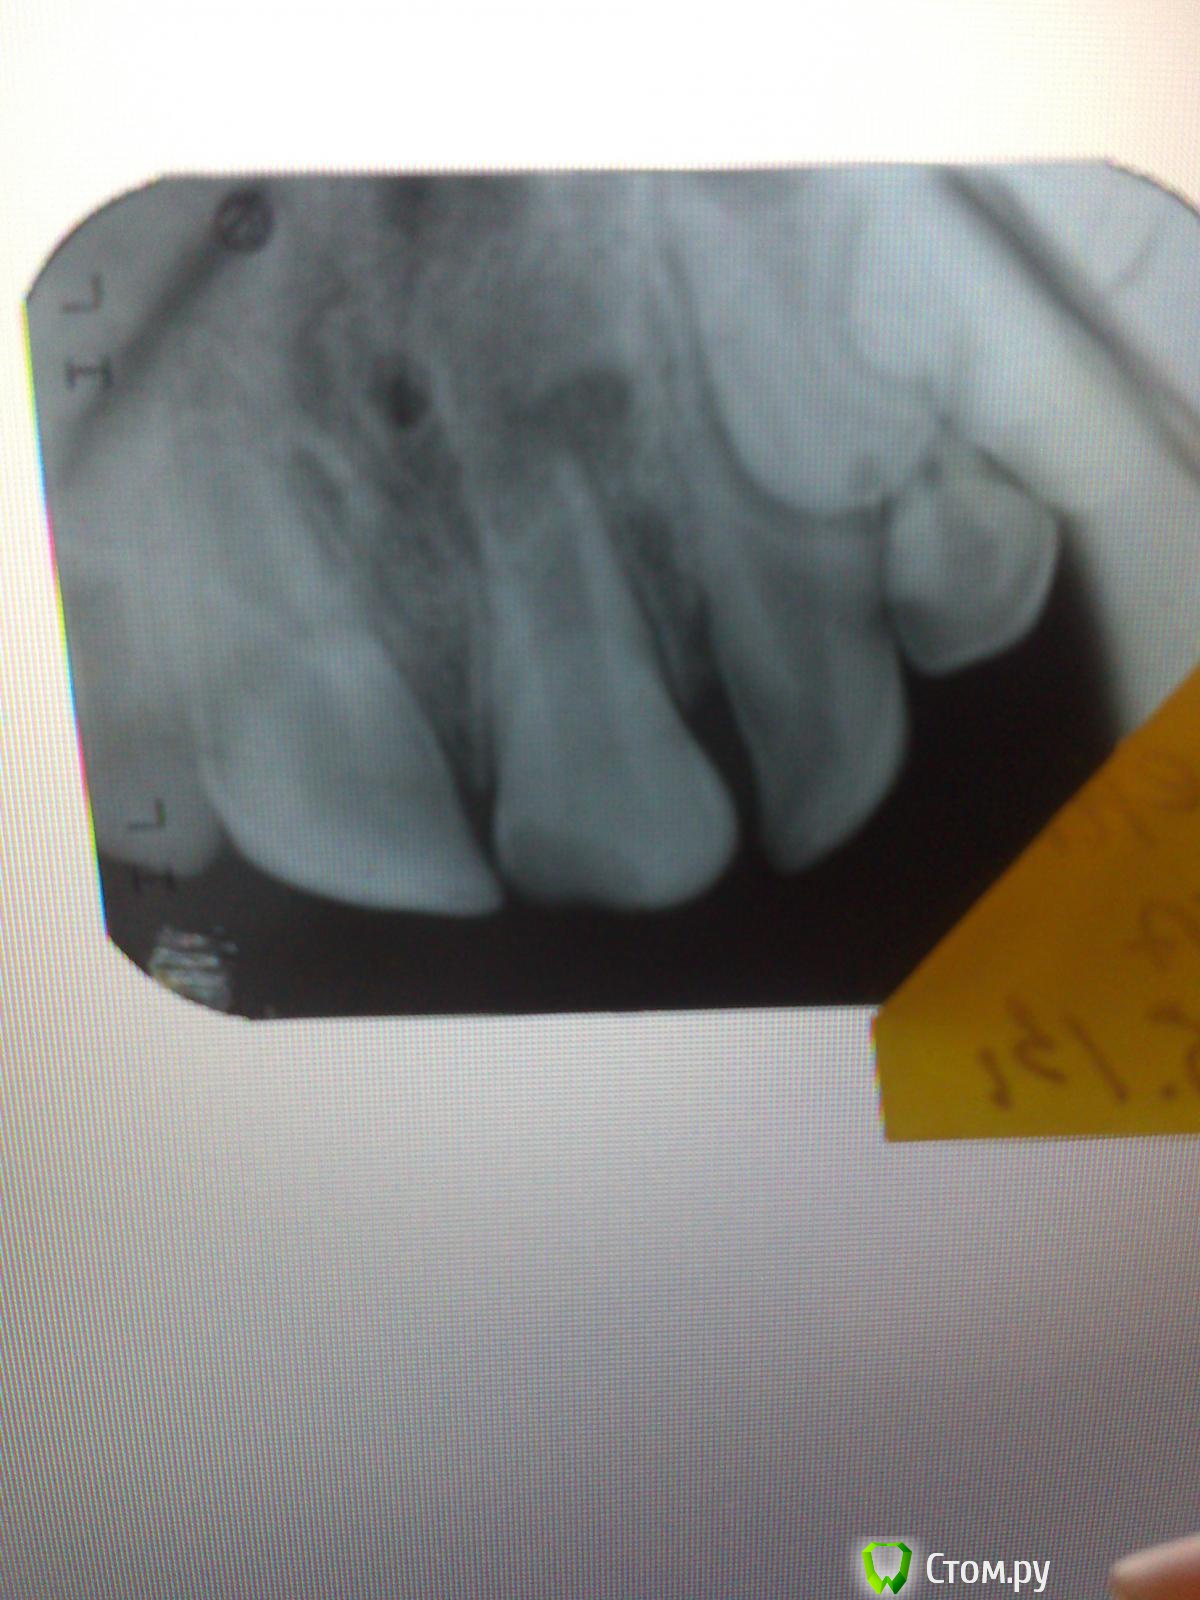

Kykysyavika Опубликовано 27 января, 2014 Поделиться Опубликовано 27 января, 2014 (изменено) В середине декабря 2013 обратился пациент 12 лет с жалобами на боли при накусывании в области центральных резцов верхней челюсти, припухлость верхней губы. Из анамнеза: более двух лет назад была травма зуба 21, скол медиального угла коронковой части. Лечение не проводилось. Жалоб не было, но, как выяснилось, зубом этим "не пользовался". пищу откусывал только правой стороной.На снимке: разрежение костной ткани диаметром 7-8 мл. Полость зуба вскрыла, экссудат прозрачный, немного желтоватый, отмыла гипохлор, ХГ, оставила пульпосептин. Отправила на разрез. Хирург назначил а/б терапию, НПВП, антигистамин.За две недели несколько раз мыла, оставляла пульпосептин- все отлично. Экссудата не было, жалоб не было.На прошлой неделе запломбировала Метапастой. Результат- обострение. Не стоило за этот зуб вообще браться? Изменено 27 января, 2014 пользователем Kykysyavika Ссылка на комментарий

Kykysyavika Опубликовано 27 января, 2014 Автор Поделиться Опубликовано 27 января, 2014 АБ были месяц назад, амоксиклав. И действительно всё было спокойно, до Метапасты. Скорее всего вывела за апекс,да еще гуттой придавила...Сейчас у пациента свищ, (или не свищ???) зуб оставила открытым, (полетели тухлые помидоры)) .Там гной с прожилками крови. Завтра попробую снова закрыть с пульпосептином.Ошибка в выводе кальция за верхушку? Ссылка на комментарий

Kykysyavika Опубликовано 28 января, 2014 Автор Поделиться Опубликовано 28 января, 2014 Я так поняла, это фото -после обострения после матапасты? А разрез был -до. А то , что на фото -как по мне -"зреет свищ"- и вот-вот вскроется, достаточно зондом "ковырнуть" и польёт, согласна с anvladd. Может ошибаюсь.Сегодня должен быть этот пациент. Если свищ вскрылся, то, вы советуете, пломбировать? Канал широкий, верхушка 35. Материалов у меня не широкий выбор. Есть МТА триоксидент, но ним или цементом не рискну, т.к нет рентгена, а пока они съездят на снимок и вернутся... Вдруг понадобитсрь распломбировка? и опыта работы у меня с ним нет. Я думала Кальций,а потом гутта с Канасоном. Ссылка на комментарий